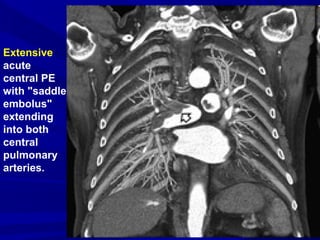

Extensive

acute

central PE

with "saddle

embolus"

extending

into both

central

pulmonary

arteries.